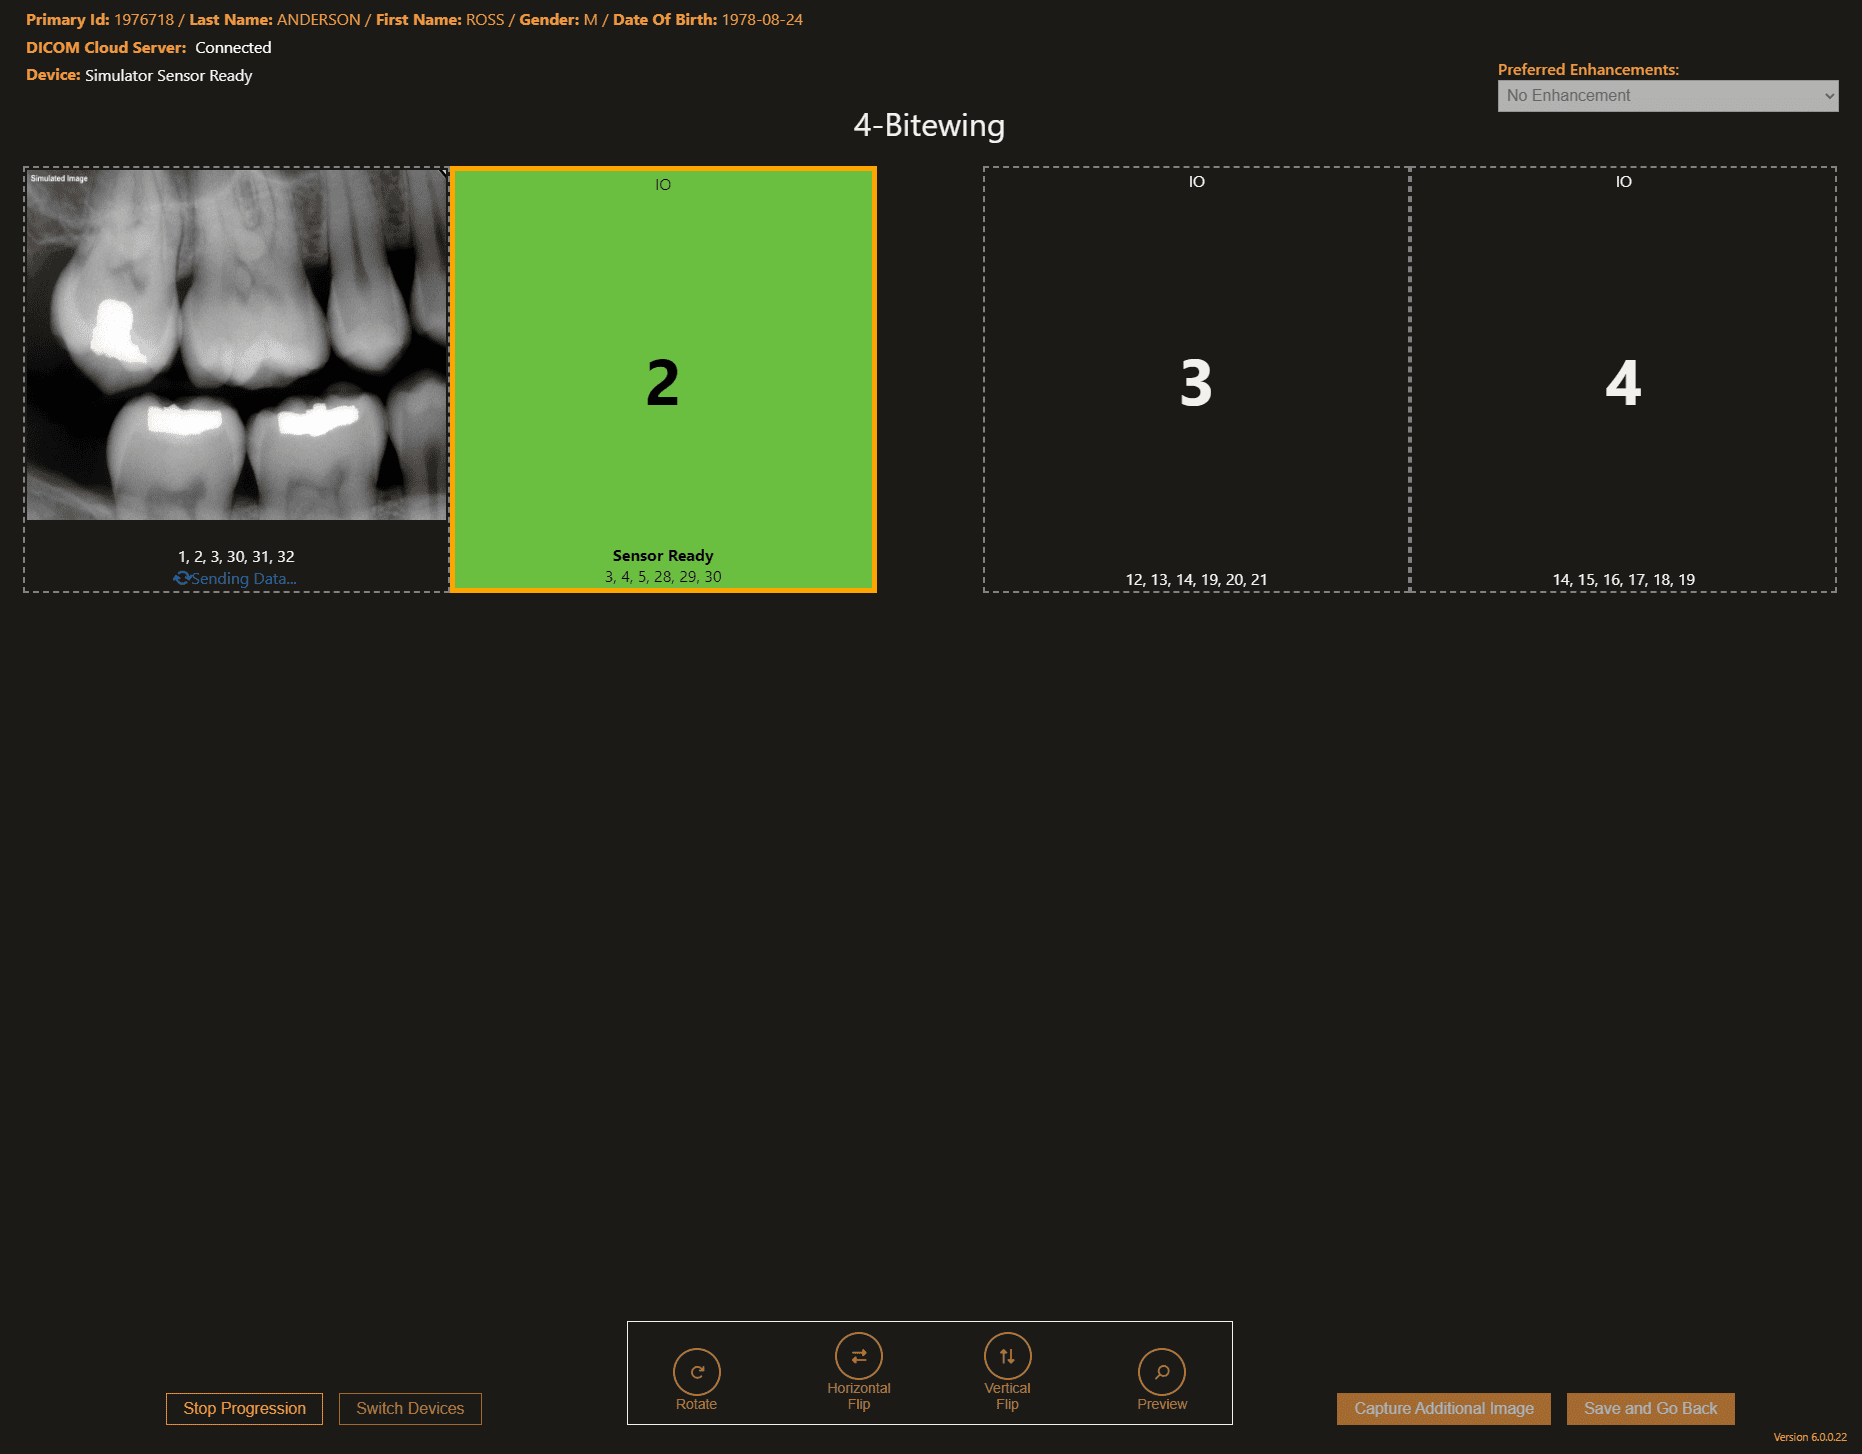

You have the freedom to use imaging devices from a wide range of manufacturers. With our open architecture philosophy, we believe you should have maximum flexibility to choose the best solutions for your practice. Benefit from sensor and practice management agnostic integration, ensuring compatibility with a wide range of sensors and solutions. Save images in the universal DICOM format and work with the imaging devices and solutions that best suit your practice.

Better Workflow with Fewer Clicks

Apteryx simplifies your entire imaging workflow, making it easier to capture, view, and enhance your images with fewer clicks. Its user-friendly interface allows for straightforward navigation and image manipulation, improving efficiency and patient care. Transition from outdated imaging systems to a seamless imaging experience.

Device Agnostic

Apteryx embraces open architecture, encouraging you to choose the hardware and software best fit for you!

PMS Integration

Apteryx allows you to bridge patient information from a wide variety of patient management software packages to your digital imaging software.